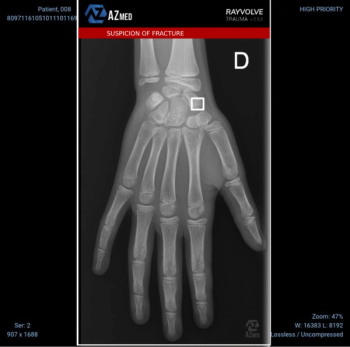

The AI-enabled software Rayvolve reportedly demonstrated a 96 percent sensitivity rate for diagnosing pediatric fractures in a recent study involving 3,000 patients.